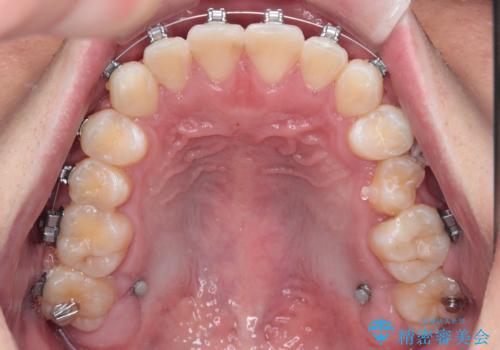

・費用と期間を抑えるために、多少目立っても効率の良いメタルブラケットを使用

・奥歯のシザーズバイト改善には、口蓋側にアンカースクリュー(TAD)を設置し、矯正用ゴムで内側に牽引

・捻転した第二小臼歯は、ワイヤーと矯正用ゴムの力を用いて正しい位置へ回転移動